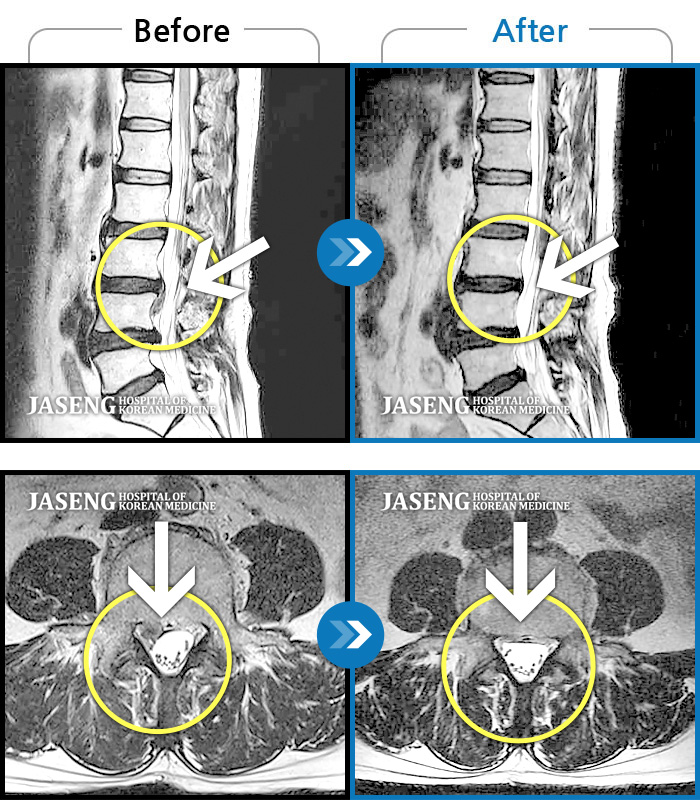

허리디스크

안산 · 김민수 원장

왼쪽 허리에서 다리로 내려가는 심한 통증으로 서 있거나 오래 걷지 못하였습니다.

촬영시기

2022.02.12 ~ 2023.02.17

2023.02.24